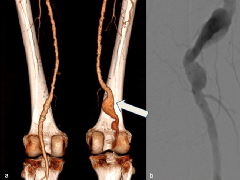

• 下肢CTA—评估疑似创伤性和非创伤性血管异常病变

下肢CTA—评估疑似创伤性和非创伤性血管异常病变